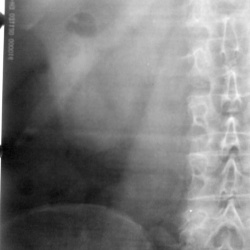

Женщина 60 лет. Оперирована справа. Аллергик, экскреторная урография не выполнялась. Слева на уровне L4 артефакт пленки. Обзорная цистография сделана отдельно - чисто.